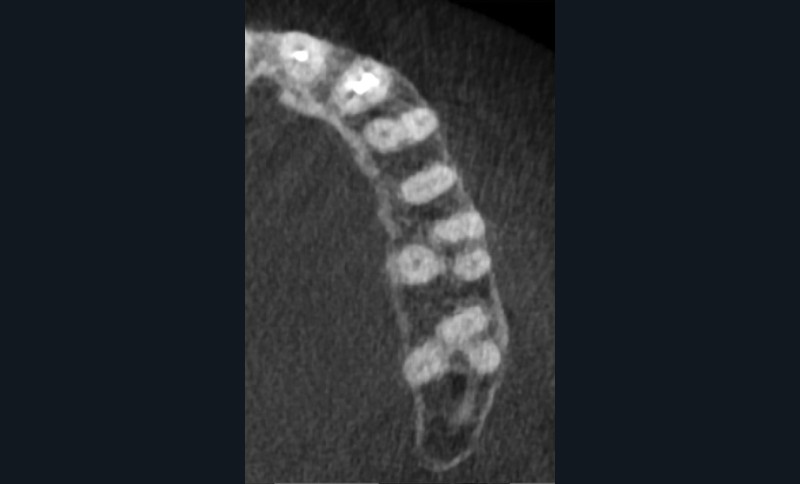

L’utilisation du scanner, et maintenant du CBCT, bouleverse l’idée très radiographique que nous avions du système canalaire.

En effet, la culture endodontique, fondée sur les critères radiographiques, a fait oublier les études de Hess et Zurcher (1925) qui mettent en évidence la complexité du système endo-canalaire [1]. Ce système présente une cavité principale (par exemple, le canal principal) ainsi que des canaux accessoires/latéraux. 25 % de ces microcanaux peuvent être interconnectés les uns aux autres, avec une densité plus importante de ramifications dans la région apicale du canal principal [2].

Rebondissant sur l’imagerie 3D et la mise en évidence des anatomies canalaires complexes, Peters, en 2001, décrit l’insuffisance instrumentale dans le traitement endodontique, et montre que 35 % des surfaces sont intactes après préparation canalaire correctement menée [18].

Endal, en 2011, montrait également, en utilisant le micro CT Scanner, l’insuffisance de nettoyage des isthmes inter-canalaires à nos techniques conventionnelles [19]. L’utilisation du laser Er:YAG devenait alors incontournable dans le nettoyage de ces isthmes et des zones non instrumentées (fig. 2 et 3).

L’anatomie complexe du système canalaire et la pénétration difficile des irrigants [26] limitent la capacité de nettoyer, débrider, et désinfecter en trois dimensions le réseau endodontique.

Si l’étude de Peters [18] nous montre que l’instrumentation laisse 35 % du volume canalaire non instrumenté, Ricucci et Siqueira montrent que la préparation physico-chimique n’élimine que partiellement les tissus nécrotiques à l’entrée des canaux latéraux, des isthmes et des ramifications apicales, en laissant des tissus enflammés et infectés, en association avec des lésions apicales [29] (fig. 4 et 5).

Fig. 4 – Coupe d’une racine mésiale de molaire mandibulaire avec deux canaux traités. Coupe à 3 mm de l’apex, coloration Brown et Brenn, technique modifiée par Taylor. Ces images montrent un isthme étroit avec une infection bactérienne, ce qui prouve l’importance de désinfecter et d’inclure l’isthme dans les traitements conventionnels et dans les rétropréparations apicales en chirurgie endodontique.